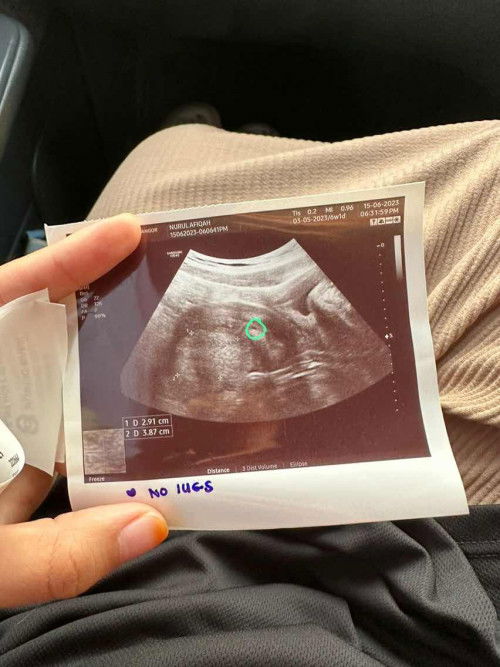

Ada fybroid masa scan 6w

Hi, saya scan time baby usia 6w1d. Tergerak hati nak scan, kantung ada dah tapi kecik lagi macam baru nak jadi. Tapi ada fybroid atau cyst pula dekat dalam rahim. Risau nya saya. Dahlah first pregnancy ni 🥺 Ada ke mommies alami masalah macam saya? #advicepls